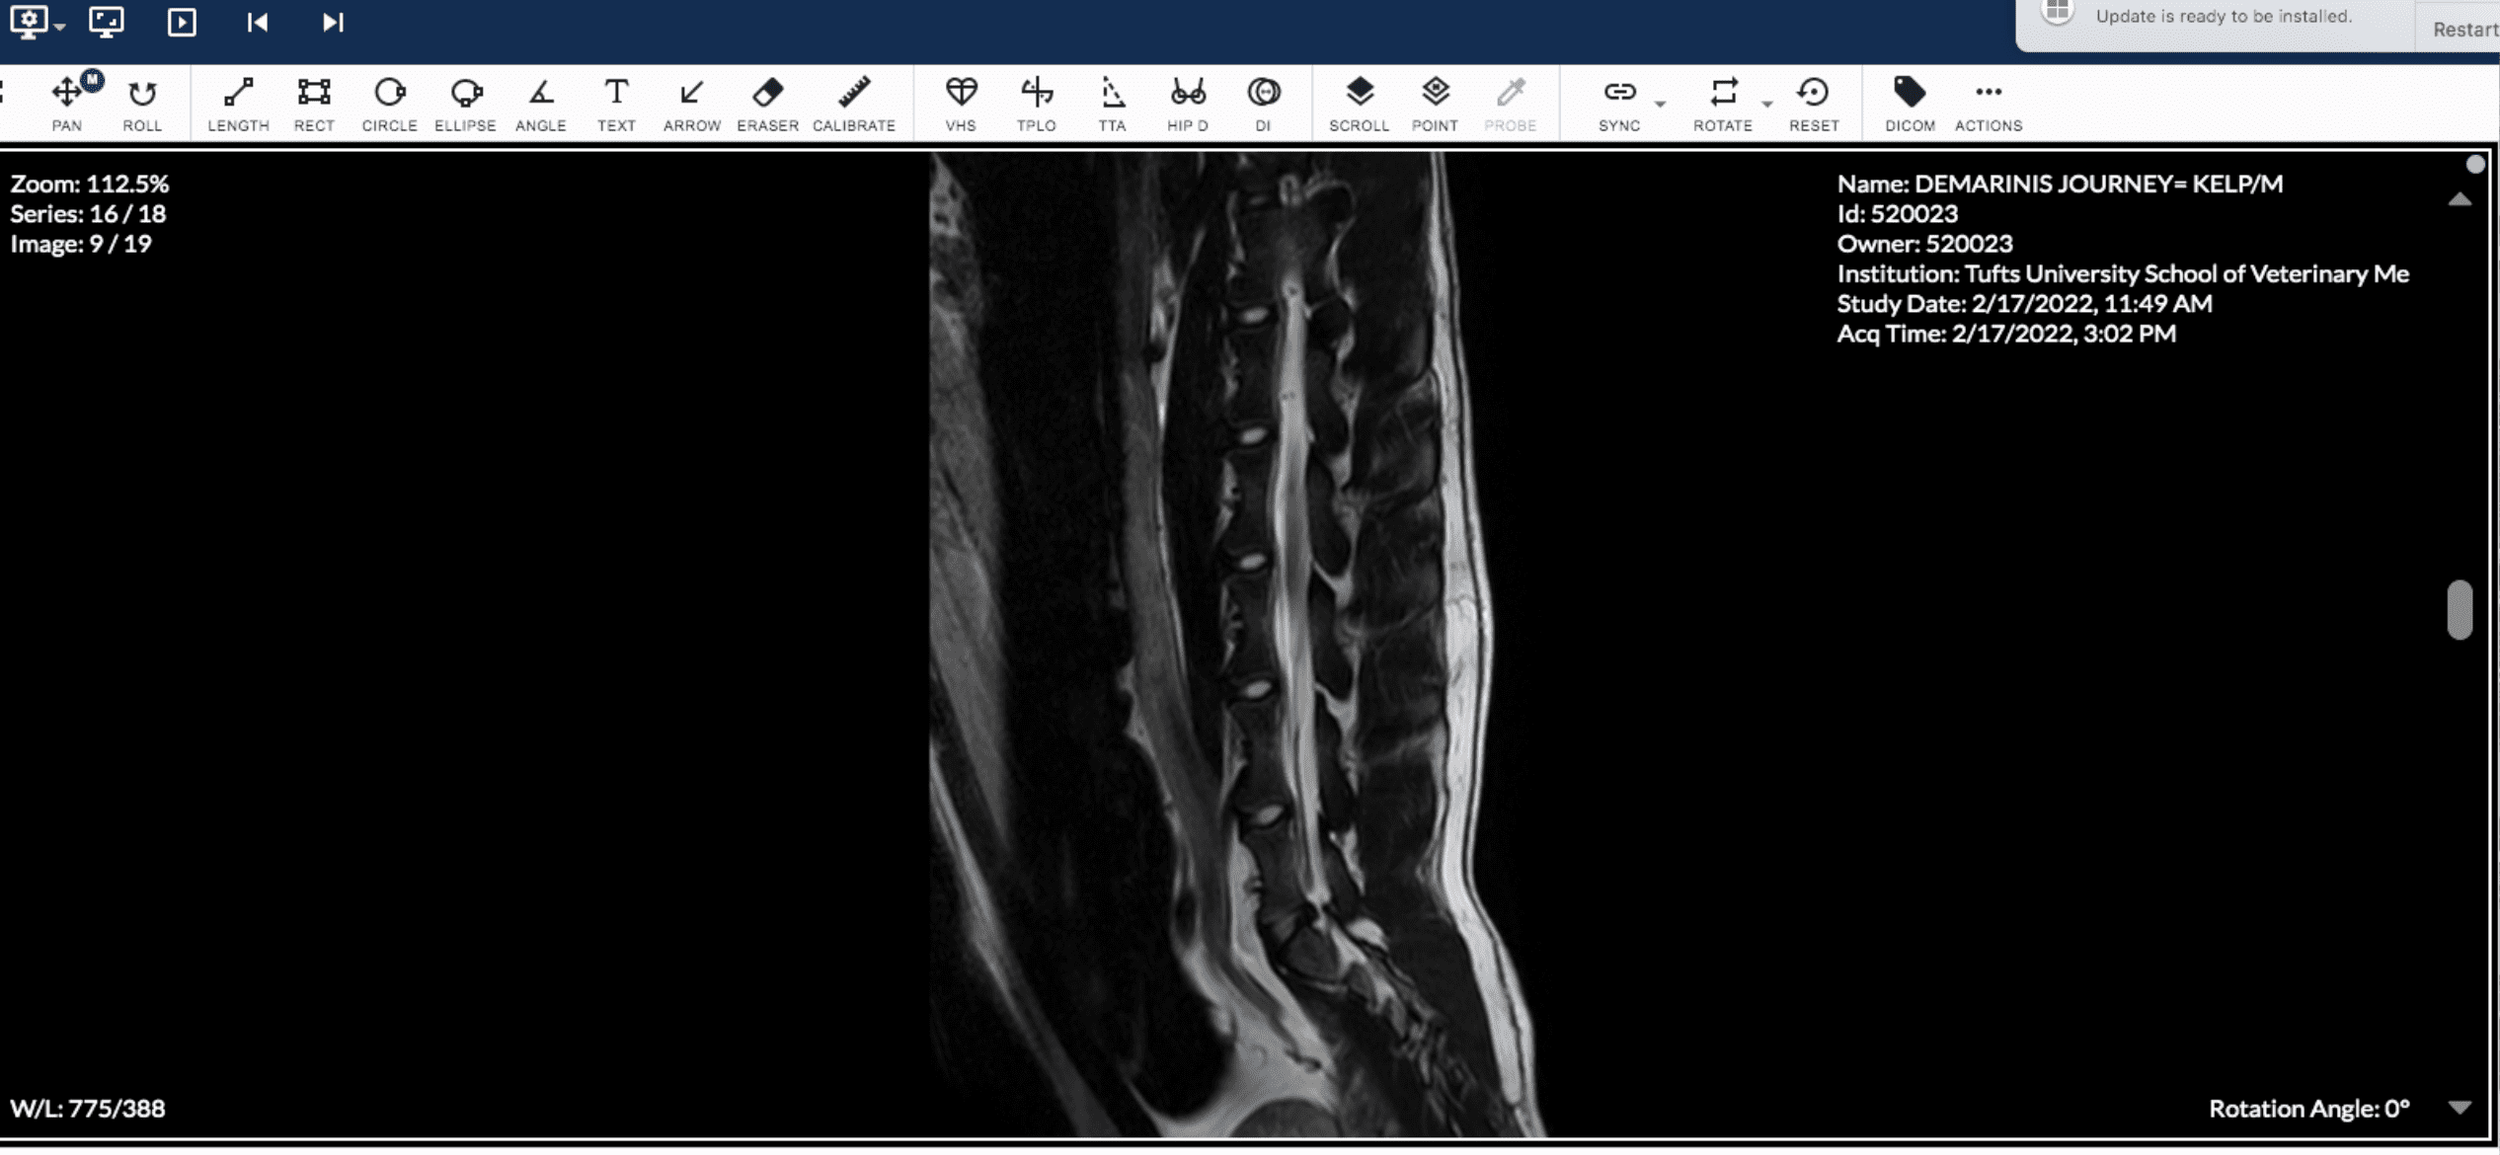

On 2/17/22 at 7:30am I dropped Journey off for his MRI. I was a nervous wreck. At 9:00am a vet technician emailed me asking for the video footage I had of Journey's episodes so that the board certified neurologist could take a look at them. At 3:30pm, the neuro resident called to update me. She said that the neurologist performing the MRI reviewed the videos as well as his brain scan. The brain scan was clear! Nothing abnormal showed up. BUT, the neurologist noticed after observing the videos that Journey seemed to display more of his episodes towards his lumbar/rear area, so the neurologist decided she wanted to do a lumbosacral MRI (an MRI of his lumbar/rear area). They identified that it was very possible he has a rare condition called Tethered Cord Syndrome. They couldn't rule out whether he also had Epilepsy, but based on the findings of the MRI, it seemed that the episodes Journey was having was related to Tethered Cord Syndrome.

Some of Journey's MRI Images of Tethered Cord

Screenshot of Journey's MRI Imagery